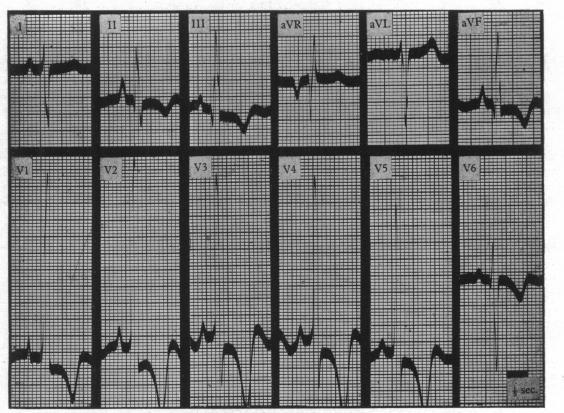

Unipolar electrocardiography in pulmonary stenosis.

Br Heart J. 1951 Jan;13(1):89-101. doi: 10.1136/hrt.13.1.89.